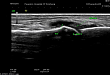

2021.01.07 新郑市人民医院肌骨超声——痛风诊断与治疗的听诊器

没有规律的疼痛,时高时低的尿酸值,不太明确的诊断,怎么办?下面带您了解痛风诊断与治疗的听诊器——肌骨超声。病例分享 1男,52 岁,左足大母脚趾处疼痛难忍 1 天来我院内分泌科就诊,既往曾有血尿酸增高